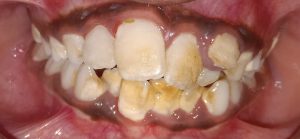

We at the Department of Pediatric & Preventive Dentistry focus on comprehensive oral health care needs of a child from infancy to adulthood and provide comprehensive, therapeutic as well as preventive care to all children including those with special care needs.